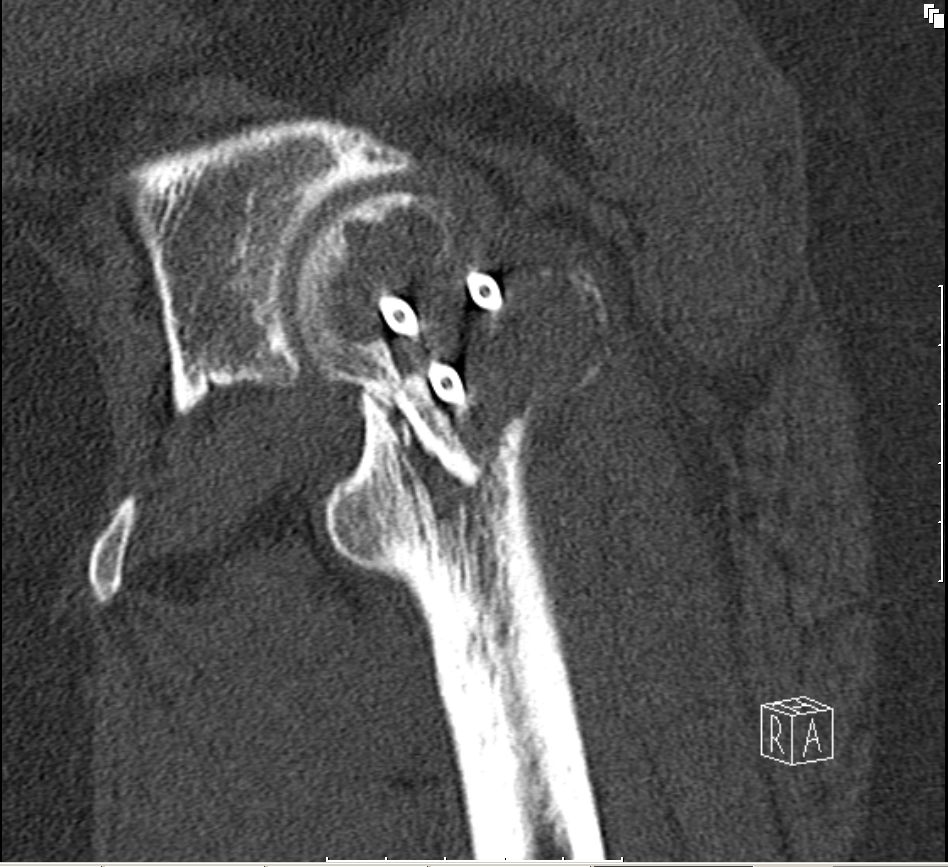

| Das CT zeigt lytische Bezirke. | ![]() | |